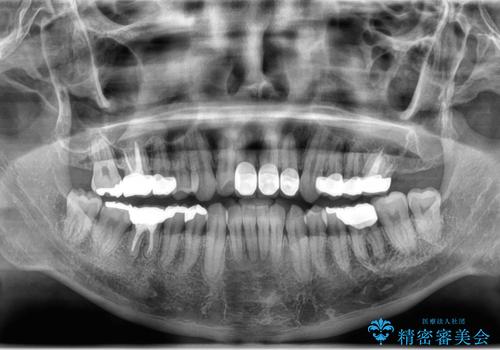

- 突き出た前歯の角度の改善と虫歯治療の改善を求めて来院されました。

虫歯を除去したのち、マウスピース矯正治療を行い、歯並びやがたつきを改善したのち、セラミックに置き換えることで審美性の向上を計画します。

矯正や虫歯治療、セラミック治療といった複合的な治療を一医院で行うことができるのが当法人の大きな特長です。